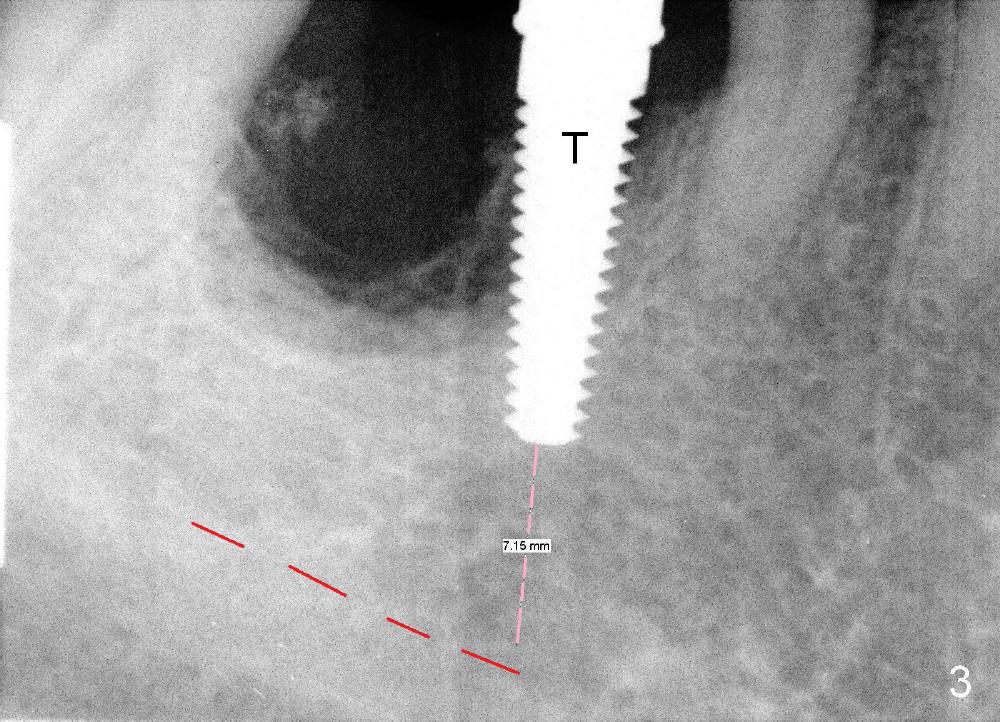

Fig.3 shows a 4.5x17 mm tap in the mesial socket (not stable). There is 7.14 mm bone between the end of the tap and the upper border of the inferior alveolar canal (red dashed line). The coronal end of the septal bone (Fig.4 >) is as high as the mesial crest.